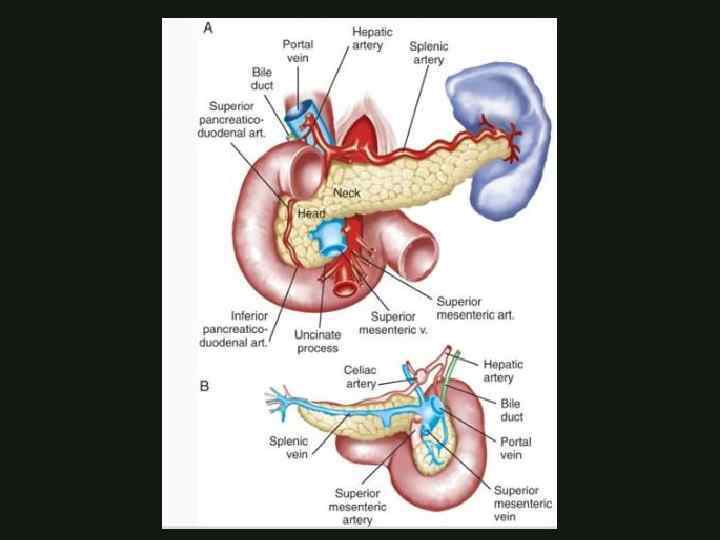

КЛАССИФИКАЦИЯ ОСТРОГО ПАНКРЕАТИТА По распространенности поражения: - мелкоочаговый - крупноочаговый По локализации: - с поражением головки - тела - хвоста - всех отделов поджелудочной железы

КЛАССИФИКАЦИЯ ОСТРОГО ПАНКРЕАТИТА По распространенности поражения: - мелкоочаговый - крупноочаговый По локализации: - с поражением головки - тела - хвоста - всех отделов поджелудочной железы